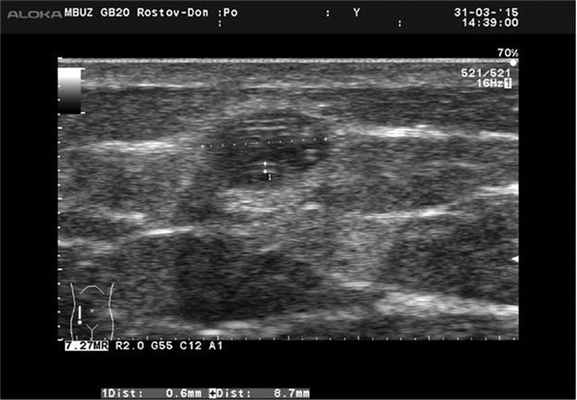

Ультразвуковое исследование на аппарате Aloka Prosound 6 линейным датчиком в В-режиме: в мягких тканях левой ягодицы на глубине 7 мм от поверхности кожи определяется полостное объемное образование округлой формы диаметром 15-8 мм, с четкими ровными контурами, содержимое жидкостное, неоднородное за счет множества правильных геометрических фигур линейной формы повышенной эхогенности, с просветом в центре, различной длины, толщиной до 0,6 мм, интенсивно флотирующих в полости образования, особенно при легком надавливании на него датчиком (рис. 2). При исследовании в режиме ЭД признаки васкуляризации образования не выявлены. Капсула образования толщиной до 3 мм, повышенной эхогенности, четко визуализируется на всем протяжении. Заключение: новообразование мягких тканей - паразитарная киста (дирофиляриоз?).

Рис. 2. Ультразвуковая картина дирофиляриоза.